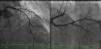

Foi admitido eletivamente em unidade hospitalar para cirurgia de circuncisão e meatoplastia. Durante a administração de ciprofloxacina, no bloco operatório, desenvolveu quadro de desconforto pré‐cordial, tipo aperto, associado a dispneia, hipersudorese e hipotensão arterial. Foi constatado aparente supradesnivelamento do segmento ST na monitorização eletrocardiográfica, suspensa a administração de ciprofloxacina e o doente foi transferido para a sala de emergência desse hospital. O eletrocardiograma mostrava supradesnivelamento do segmento ST (>3mm) em DII, DIII e aVF, com infradesnivelamento do segmento ST e inversão da onda T em aVL e V1‐V3 (Figura 1). Dada a suspeita de síndrome coronária aguda com supradesnivelamento de ST ínfero‐posterior, foi realizada medicação com dose de carga de ticagrelor (180mg), ácido acetilsalicílico (250mg) e 8mg de morfina. Foi referenciado para cateterismo emergente no nosso hospital e a coronariografia, realizada duas horas após o início das queixas, revelou ausência de doença coronária epicárdica (Figura 2). Posteriormente, foi admitido na unidade de cuidados intensivos cardíacos e na admissão não apresentava queixas, encontrava‐se hemodinamicamente estável (pressão arterial: 112/67mmHg) e o eletrocardiograma mostrou ritmo sinusal, com bloqueio de ramo direito e sem alterações do segmento ST (Figura 3). O ecocardiograma transtorácico não revelou alterações da contractilidade segmentar ou outras alterações relevantes. A avaliação laboratorial mostrou leucocitose de 11,72×103/uL (valores de referência: 3,8‐10,6×103/uL), neutrofilia (86,8%) e elevação da proteína C reativa de 5,24mg/dL (valores de referência: 0‐0,5mg/dL), parâmetros inflamatórios que normalizaram nas primeiras 24 horas. A avaliação de biomarcadores cardíacos mostrou ligeira variação de troponina T de alta sensibilidade (descida de 0,051 para 0,035ng/mL às 12 horas, valores de referência: 0,003‐0,014ng/mL) e NT‐pro‐pepti¿do natriurético B normal (102pg/mL, valores de referência: 0‐450pg/mL). Dada a ausência de doença coronária epicárdica, associada à história prévia de alergia a quinolonas e relação temporal com a administração de ciprofloxacina, foi assumido o diagnóstico de síndrome coronária aguda alérgica (síndrome de Kounis). O doente teve alta após 24 horas de vigilância, medicado com nitrato oral de longa ação e não apresentou quaisquer eventos em dois meses de seguimento.